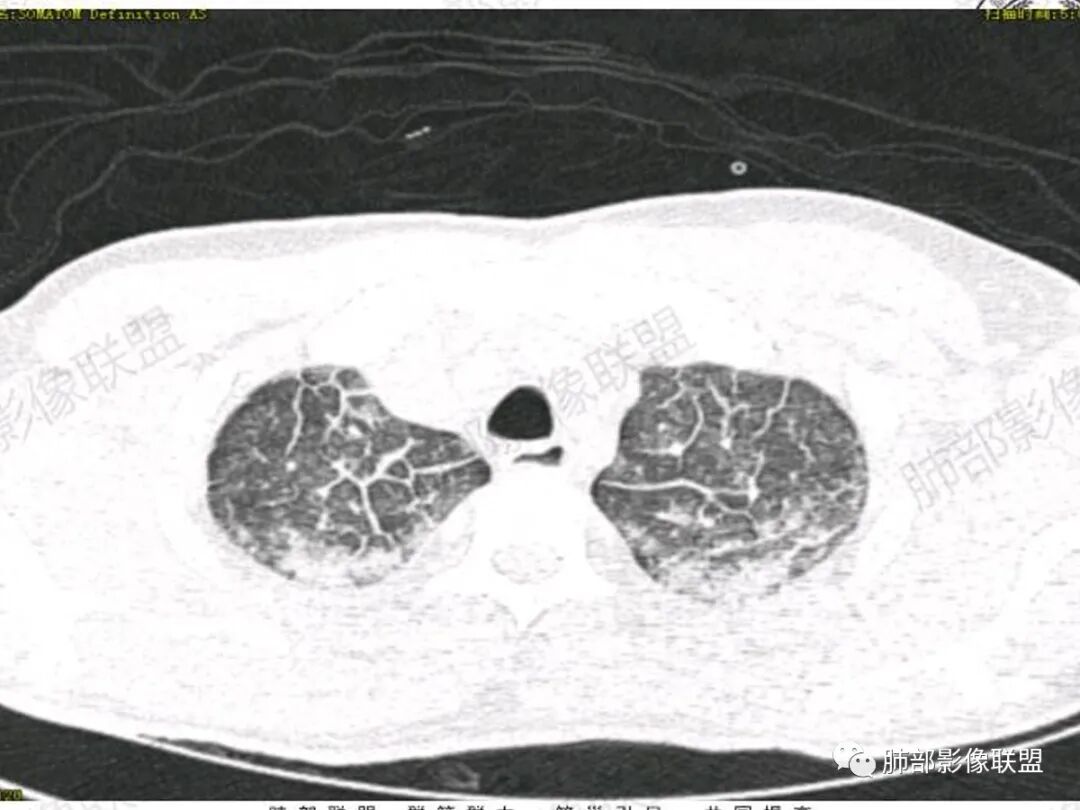

37岁男性 气促 两肺对称分布磨玻璃及小叶间隔增厚,两肺上叶后段及下叶背段为著,有重力分布,下部密度较高,请结合病史排查肺水肿,理化性肺泡损伤

双肺叶透亮度对称性减低,呈磨砂状,小叶间隔规则增厚,上叶为甚,左右肺叶中轴间质增厚(示淋巴回流障碍),双肺叶弥散磨GGO征,以肺腺泡分布,双肺上,下叶融合片状,有重力分布特点,心脏大,肺动脉干增粗,首选心源性肺水肿,但无胸腔积液。与急性肺损伤和ARDS鉴别

影像:两肺上叶小叶间隔增厚,斑片,腺泡结节,重力分布,下肺不累及

青年男性,气促7小时入院,意识模糊,白细胞及中性粒明显增高,PCT增高,CRP不高,心率快,体温正常,血压正常。胸部CT:双肺上叶小叶间隔光滑增厚,中轴间质增厚,弥漫性磨玻璃、多发斑片影,以上肺、背侧分布为主。影像表现考虑为肺水肿。病因:病史不支持肾功能衰竭、心源性、高原性肺水肿,无发热,似乎也不支持细菌、病毒、真菌等感染引起。吸入毒物?吸入水?

对称性小叶间隔增厚

高密度影重力趋势

病灶的分布以上肺为主

结合病史,最终诊断是 “急性烟雾吸入性肺损伤”,影像学表现主要是肺水肿及弥漫性肺泡损伤改变,因为烟雾气体吸入肺内分布以上肺显著,因此影像学表现也是累及上肺更明显。损伤因素包括大量一氧化碳 二氧化碳 一氧化氮等燃烧产生的有毒气体,也有烟雾粉尘颗粒对气道黏膜的损伤。